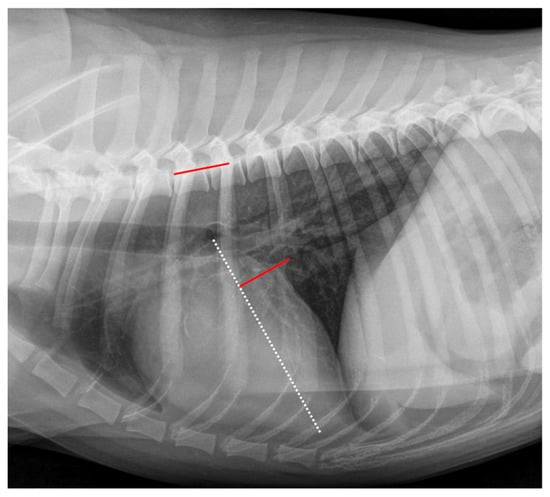

2.4. Radiographic Measurements